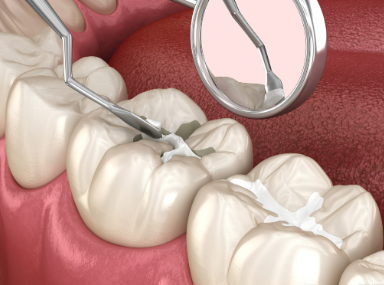

儿童齿科涂氟有必要吗?告诉你5个关键理由! 本文围绕“儿童齿科涂氟是否必要”展开探讨。涂氟能加强牙齿钙化、抑制细菌、增加抵抗力、避免牙病影响营养摄入。一般建议三岁后涂氟,需在医生指导下于正规医院操作。同时要注意掌握氟浓度,防止氟斑牙和氟中毒,涂氟后短时间避免进食。总体而言,涂氟有益,但要正确操作,家长可咨询医生保障孩子牙齿健康。 儿童牙齿 2026年03月04日 0 点赞 0 评论 7 浏览